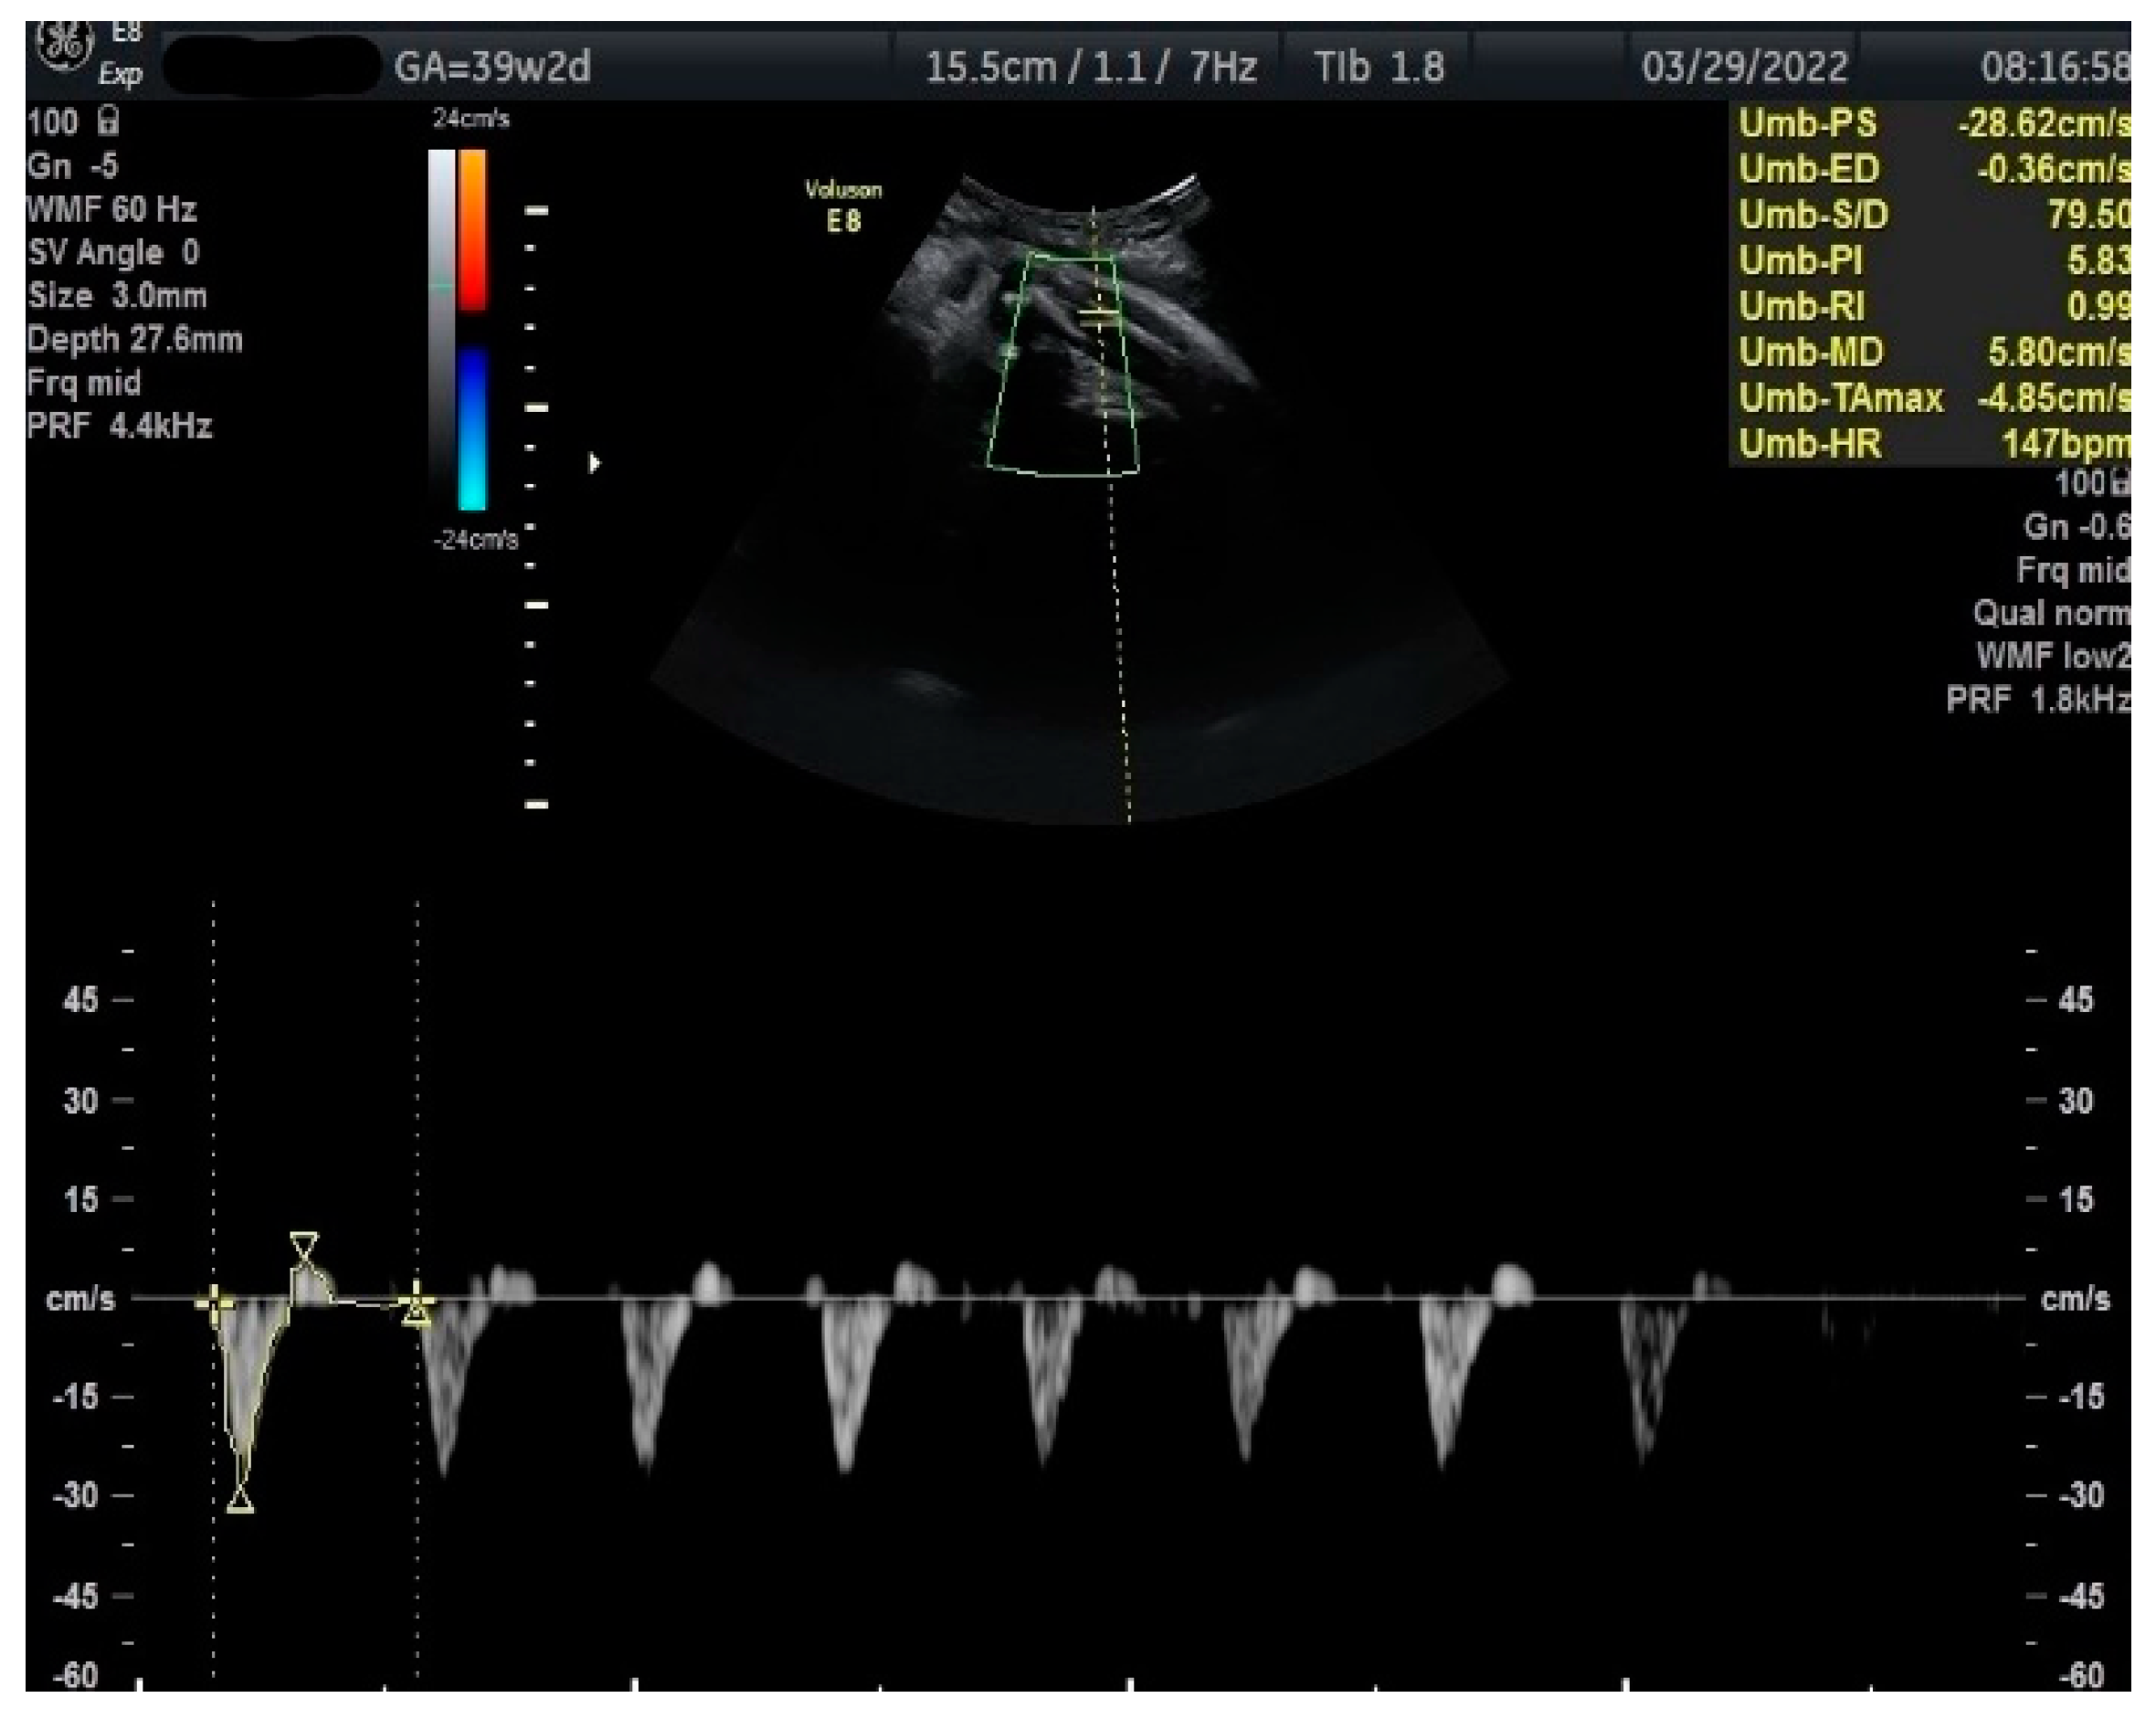

Figure 3.

Doppler measurement at 39 + 2 weeks of TA-PI shows reverse flow >95th percentile (measured manually).